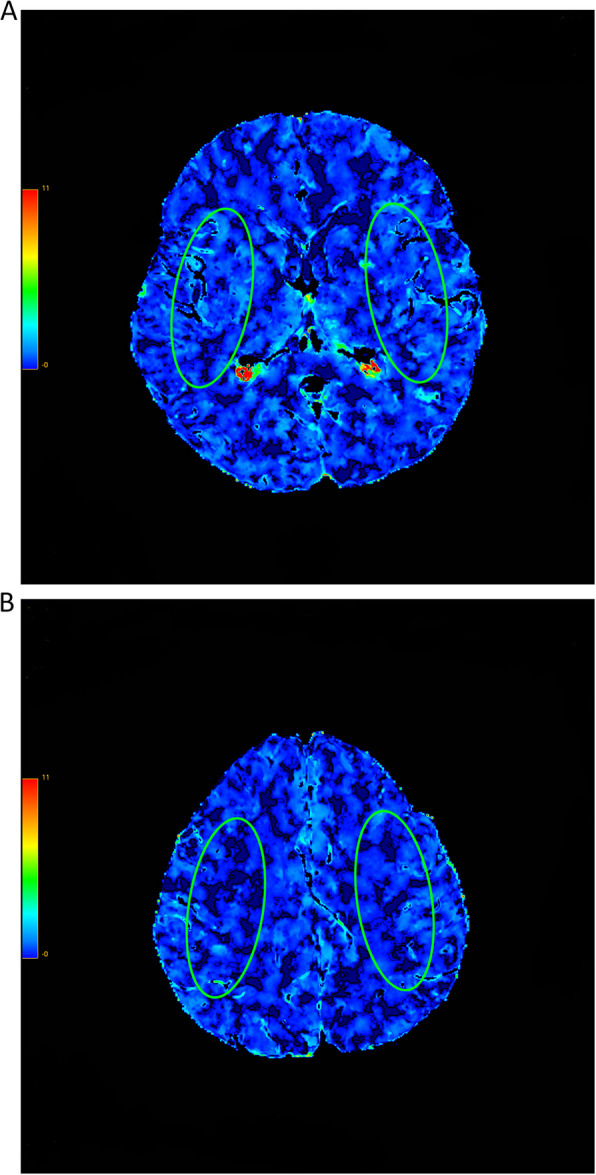

Methods: The study included a total of 17 subjects (13 men), of which bilateral carotid artery stenosis was greater than 70%. All patients underwent unilateral carotid endarterectomy. Differences in the following computed tomography perfusion (CTP) parameters were compared before and after operation: cerebral blood flow (CBF), cerebral blood volume (CBV), mean transit time (MTT), time to peak (TTP), and PS. PS acquired by CTP is used to measure the permeability of the BBB to contrast material.

Results: Before surgery, the operative side exhibited significantly lower CBF (p = 0.001) and prolonged MTT (p = 0.002) and TTP (p = 0.001) compared to the nonoperative side, while PS and CBV showed no significant differences. After carotid endarterectomy, only the operative side demonstrated improvements, with CBV increasing by 9.4%, MTT decreasing by 20.3%, TTP decreasing by 14.1%, and PS decreasing by 27.5% (all p < 0.01). No significant changes were observed on the nonoperative side.